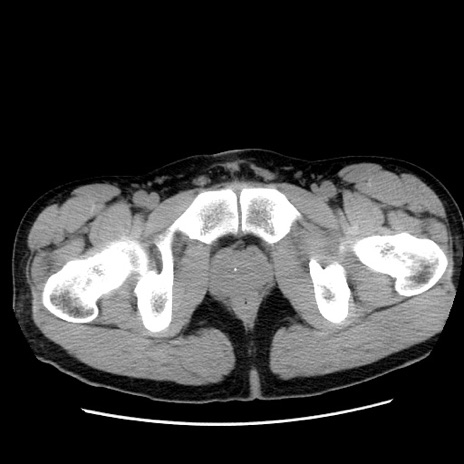

症例36(横断像)

【症例】20歳代 男性

【主訴】心窩部痛

【現病歴】今朝より上腹部痛あり。一旦軽快していたが再度出現したため救急要請。昨日夕に白身の魚を含む刺身を食べた。

【身体所見】BP 136/89mmHg、HR 74/min、BT 37.0℃、腹部:膨満、軟、心窩部に圧痛あり。反跳痛なし、筋性防御なし、腸雑音やや亢進あり。

【データ】WBC 17700、CRP 0.48